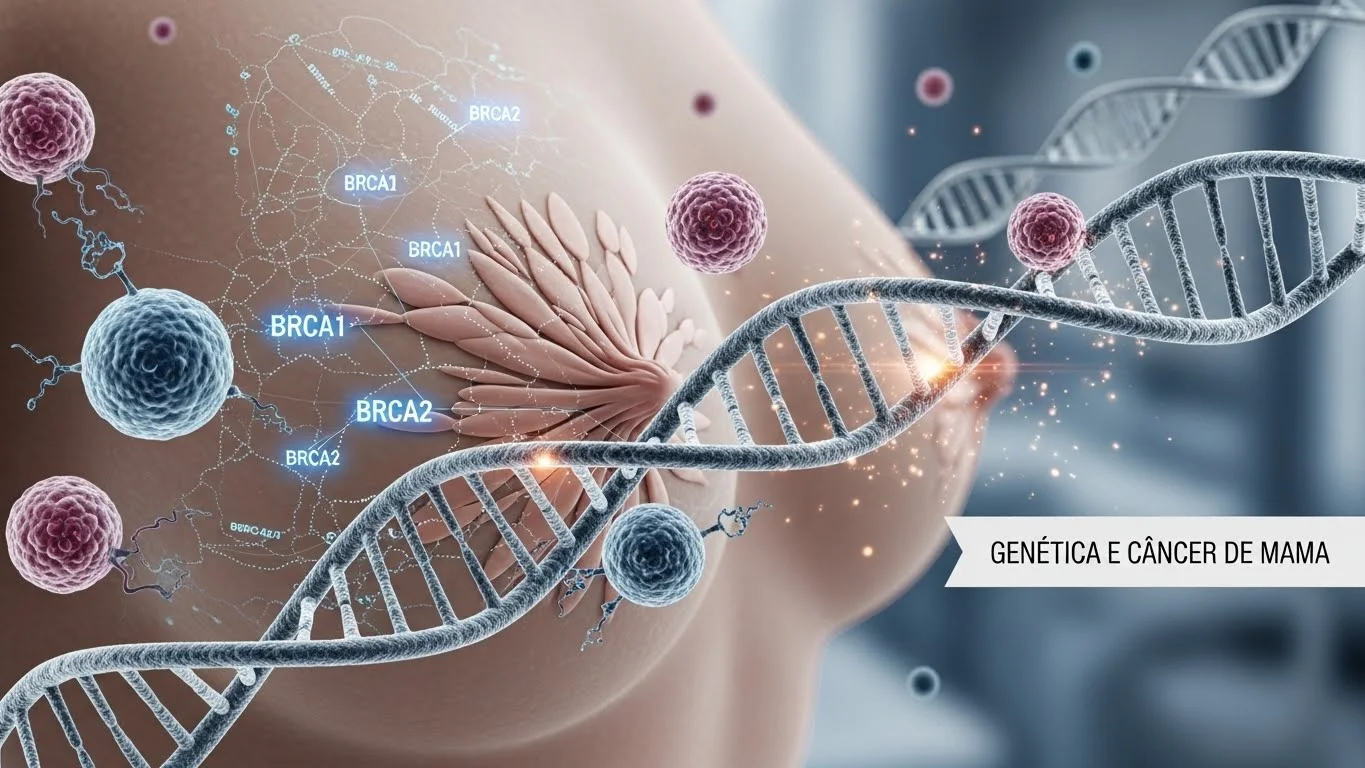

Genética e Câncer de Mama: o que você precisa saber sobre os genes BRCA1 e BRCA2 O câncer de mama...